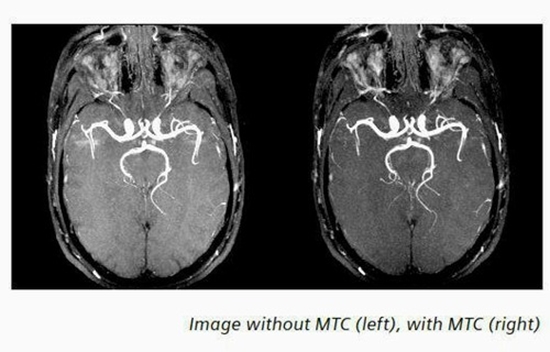

مقایسه یافته های حاصل از تکنیک 3D TOF MRAبا و بدون تزریق ماده حاجب وانژیوگرافی DSA در بررسی انوریسم های مغزی درمان شده با کویل

تکنیک 3D–TOF MRAبا و بدون تزریق ماده حاجب وانژیوگرافی DSA درانوریسم مغزی